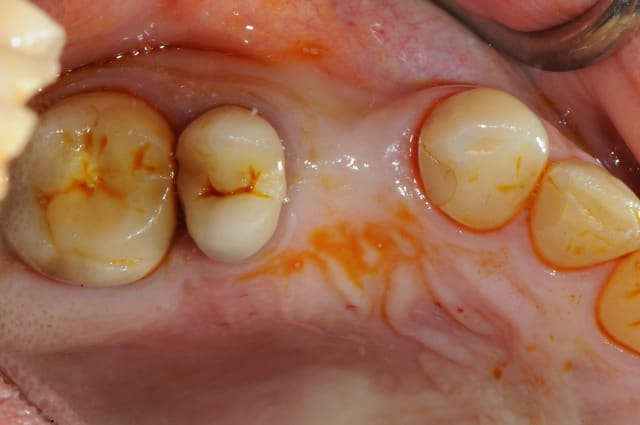

résultat à j+5

c'est pas si mal, le "greffon" est rose et ne semble pas s'être nécrosé.

attendons encore 3 mois..